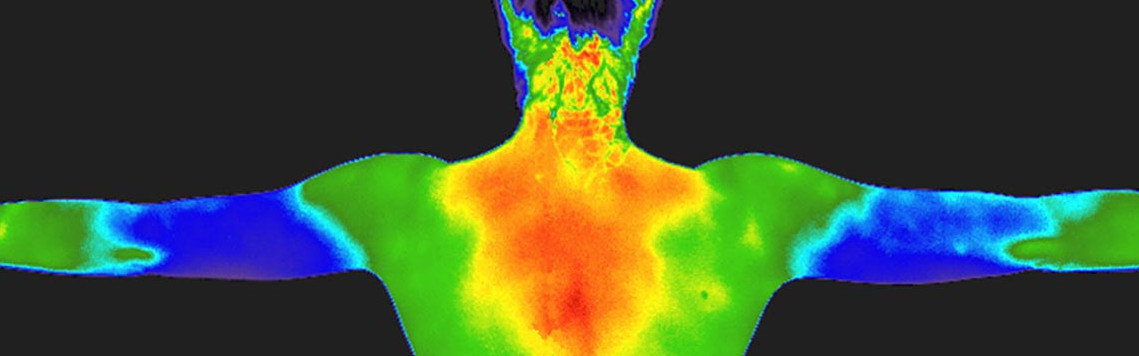

Digital Infrared Thermal Imaging

Digital Infrared Thermal Imaging, or DITI, is a totally non-invasive, painless procedure with no radiation and no contact with the body. It uses an infrared camera with a highly accurate heat sensor to detect differences in temperature in the body.